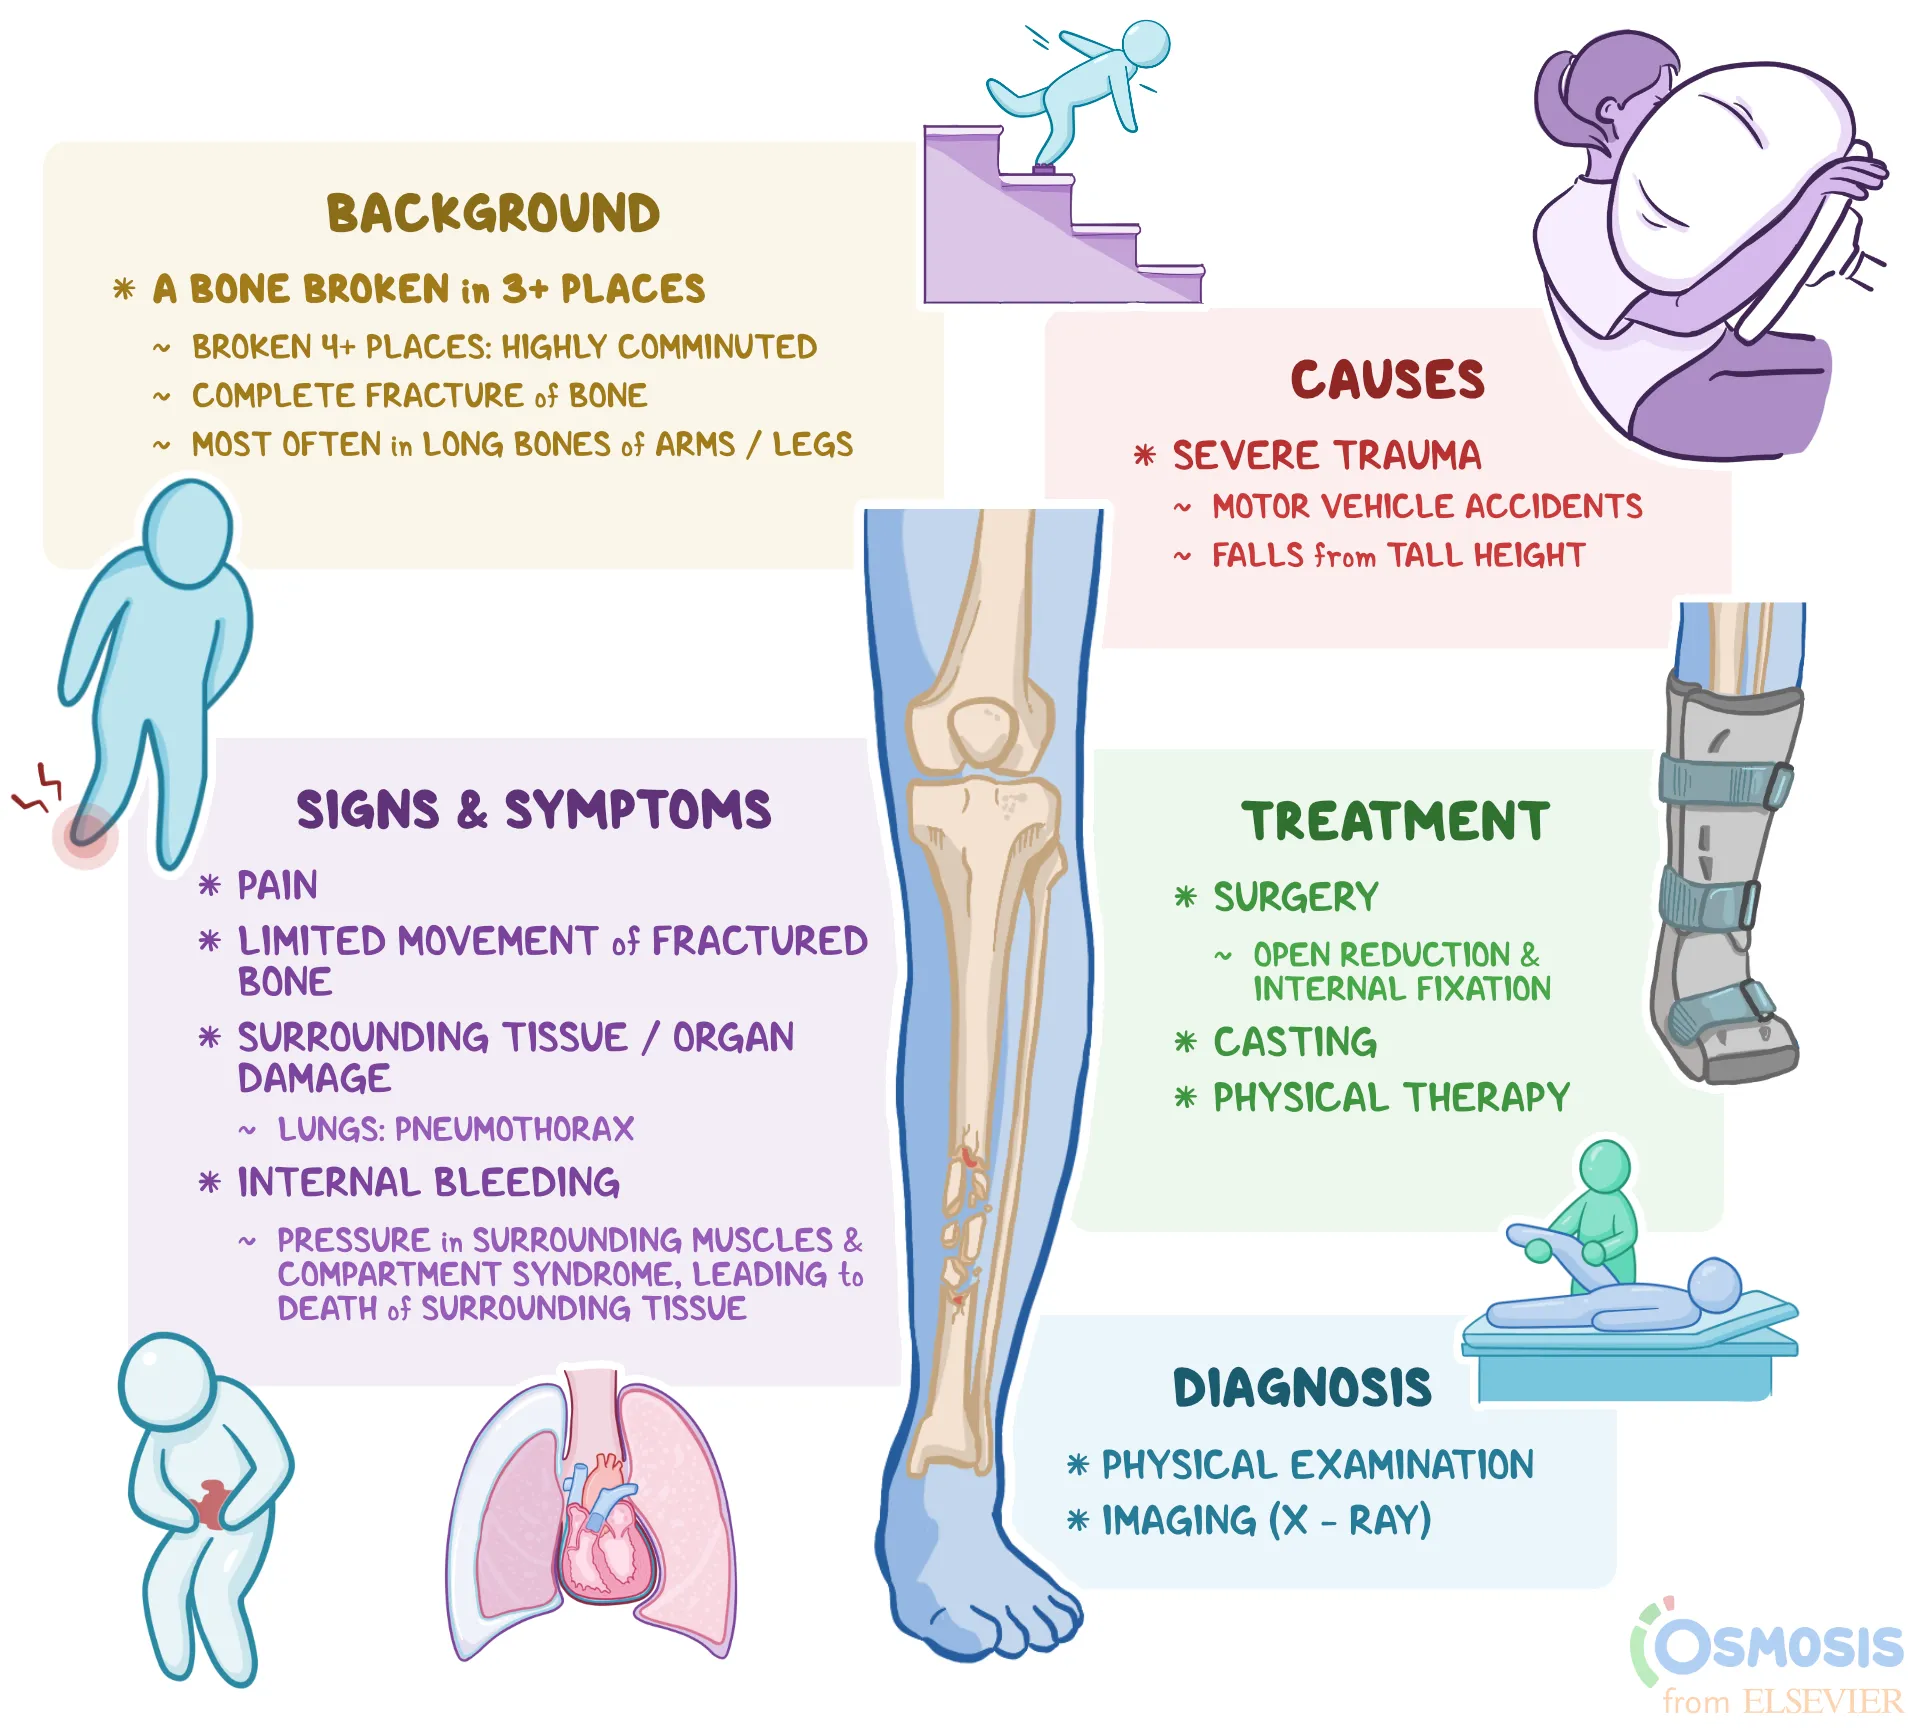

Comminuted Fracture What Is It Examples And More Osmosis

Comminuted Fracture What Is It Examples And More Osmosis